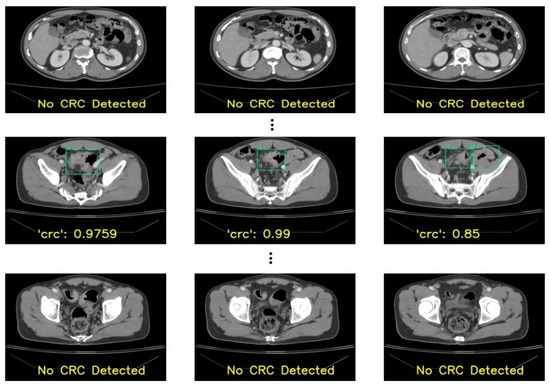

In the patients’ CT scans, the tumors were observed to be localized either in the colon or rectal regions. Irrespective of the location of the CRC, it was necessary to annotate the CRC region for training the deep learning-based detection model in a supervised manner. As a result, two radiologists with approximately 5 years of experience annotated the CRC region in the raw CCT slices using OSIRIX MD v10.0.5 (Pixmeo SARL, Bernex, Switzerland) [20] and Horos (https://horosproject.org/) (version 3.3.6) (accessed on 20 June 2021). Figure 1 shows examples of the ground truths. A total of 1558 slices were annotated out of 16184 slices in the 190 patients used for the model derivation.

Figure 1. Examples of the ground truths provided by the experts: (a,b) colon region, and (c,d) rectum region.